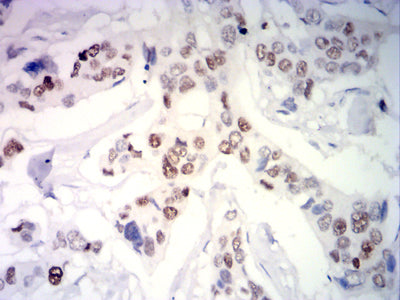

分类: 科研抗体货号: 31933别名: PR; NR3C3应用: WB,IHC,FCM反应种属: Human